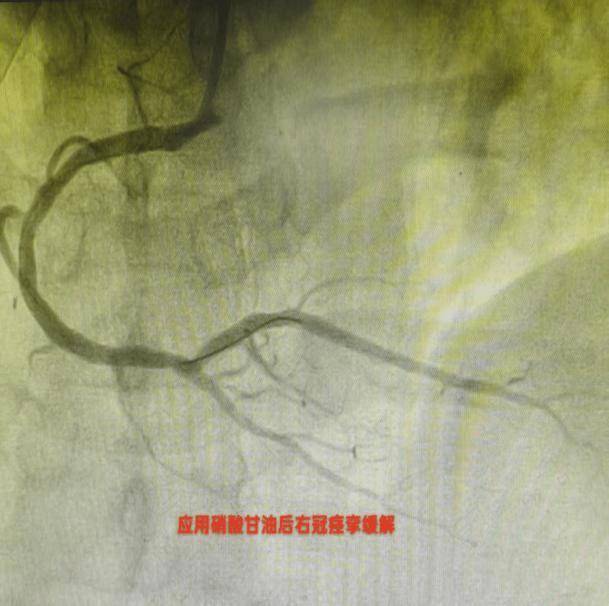

另一位40多岁的男性患者,有抽烟习惯,每日一包,平时应酬多,生活作息极不规律。春节期间,他连续多日熬夜。正月初十的清晨六点,起床后突发剧烈胸痛,被紧急送至广东省中医院大学城医院。造影显示冠状动脉三支血管严重痉挛,右冠远端重度狭窄,姚耿圳副主任医师仔细甄别,行冠脉内推注硝酸甘油并行腔内影像学检查后,避免了一次不必要的支架植入。